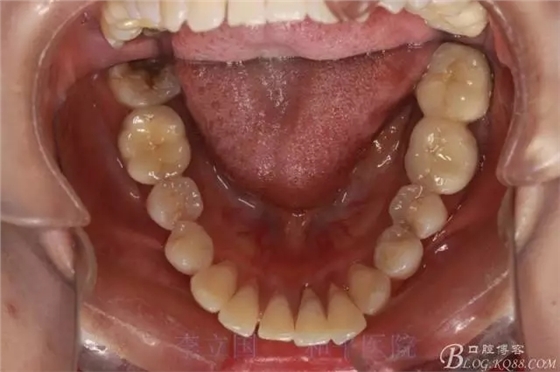

2.Damonclear排齊整平。

3.微種植支抗內(nèi)收上下前牙。

4.調(diào)整咬合關(guān)系。

治療要點(diǎn):

1.患者上前牙直立,面型前突,典型的嘴凸牙不吐,關(guān)鍵是前牙轉(zhuǎn)矩控制,建議使用高轉(zhuǎn)矩托槽。

2.磨牙關(guān)系一側(cè)完全遠(yuǎn)中,一側(cè)遠(yuǎn)中尖対尖,采用兩個(gè)上4,一個(gè)下1的拔牙模式。

3.上頜應(yīng)用支抗釘。表麻下在56牙槽間隔植入,注意因使用的為鈦合金釘,一直保持植入角度與骨面成60度角,不要垂直植入再改變角度。要求即刻加載,即刻加載力值2盎司。

4.使用長(zhǎng)牽引鉤,使?fàn)恳咏项M骨阻抗中心,防止上頜骨的順時(shí)針旋轉(zhuǎn)。

5.回收過程中,上下前牙輕搖椅,防止覆合加深。